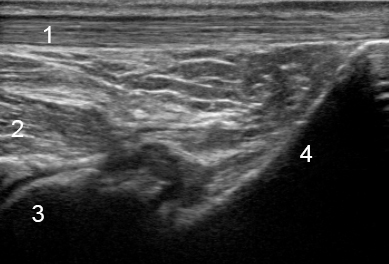

Articulación subastragalina posterior del tobillo

1. Tendón de Aquiles

2. Flexor largo del dedo gordo

3. Astrágalo

4. Calcáneo